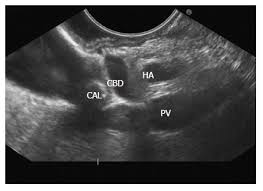

Anatomy of the gall bladder : Check 'gallbladder' translations into malay. Gross anatomy of abdomen usmle step 1the gallbladder is a gastrointestinal organ located within the right hypochondrial region. The gallbladder is lined with epithelial cells and has a strong layer of smooth muscle in its wall. Gallbladder polyps larger than 1/2 inch in diameter are more likely to be cancerous or turn into cancer over time, and those larger than 3/4 inch (almost 2 centimeters) in diameter may pose a significant. Acute symptoms are characterized by sharp, stabbing pain in the upper right side of the. In humans the loss of the gallbladder is. Bile is made up of water, cholesterol, bile salts, fats.

Anatomy of the gall bladder :